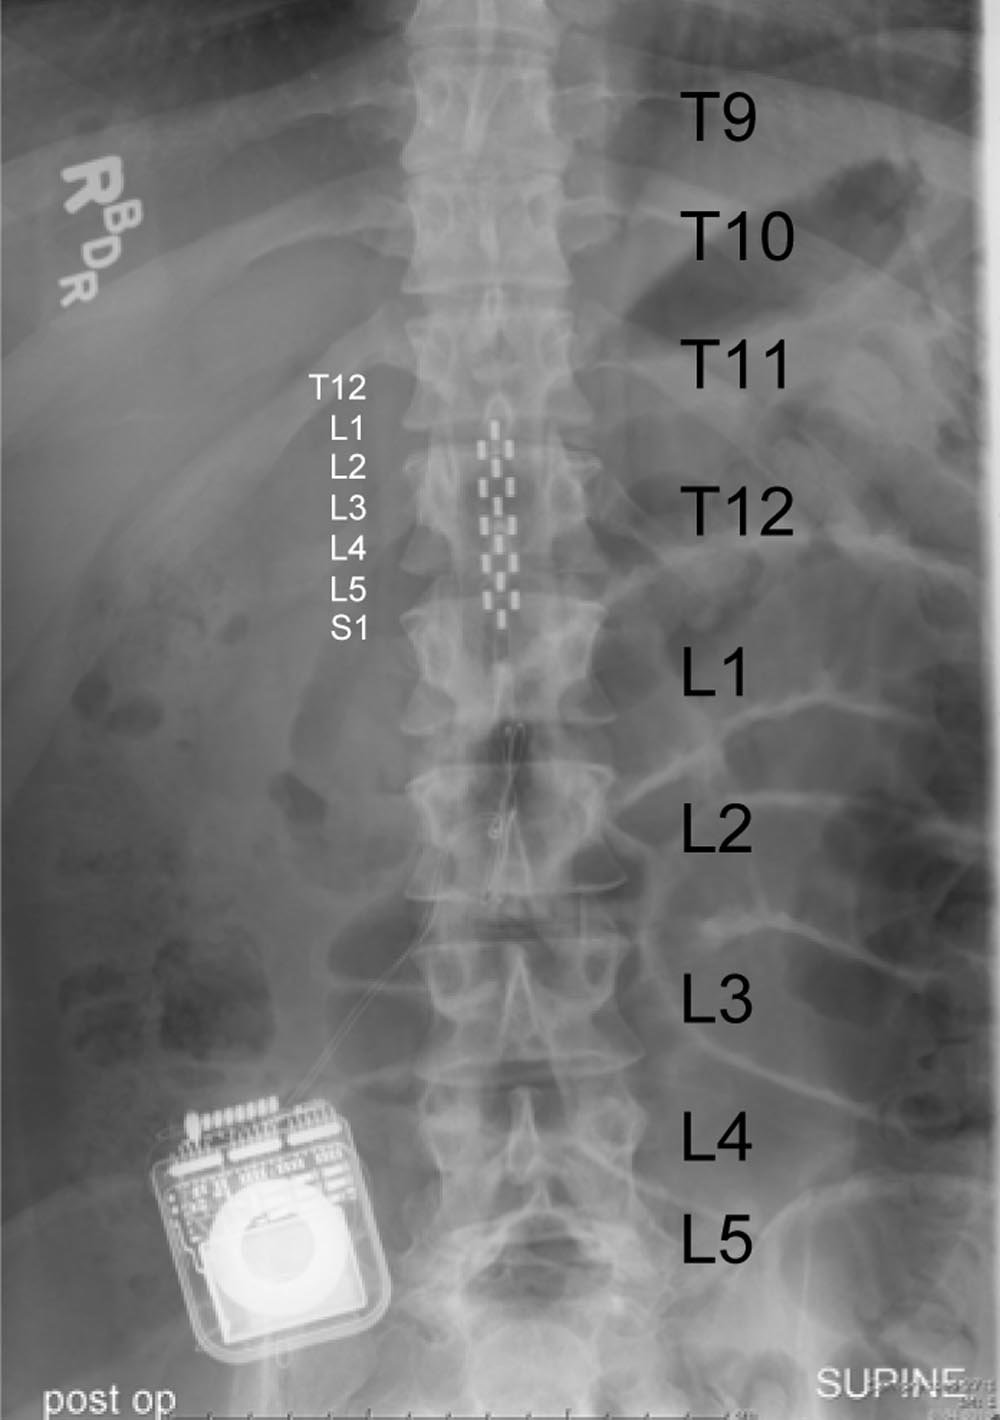

Joel Burdick, the Richard L. and Dorothy M. Hayman Professor of Mechanical Engineering and Bioengineering at Caltech, and Yu-Chong Tai, a Caltech professor of electrical engineering and mechanical engineering, helped create the therapy, which involves the use of a sheetlike array of electrodes that stimulate Summers' neurons and thus activate the circuits in his lower spinal cord that control standing and stepping. The approach has subsequently been successfully tested on a second paraplegic, and therapists are about to finish testing a third subject, who has shown positive results.

But Tai and Burdick want to keep the technology, as well as the subjects, moving forward. To that end, Tai is developing new versions of the electrode array currently approved for human implantation; these will improve patients' stepping motions, among other advances, and they will be easier to implant. Burdick is also working on a way to let a computer control the pattern of electrical stimulation applied to the spinal cord.

Because spinal-cord injuries vary from patient to patient, deploying the system has required constant individualized adjustments by clinicians and researchers at the Frazier Institute, a leading center for spinal-cord rehabilitation. "Right now there are 16 electrodes in the array, and for each individual electrode, we send a pulse, which can be varied for amplitude and frequency to cause a response in the patient," Burdick says. Using the current method, he notes, "it takes substantial effort to test all the variables to find the optimum setting for a patient for each of the different functions we want to activate."